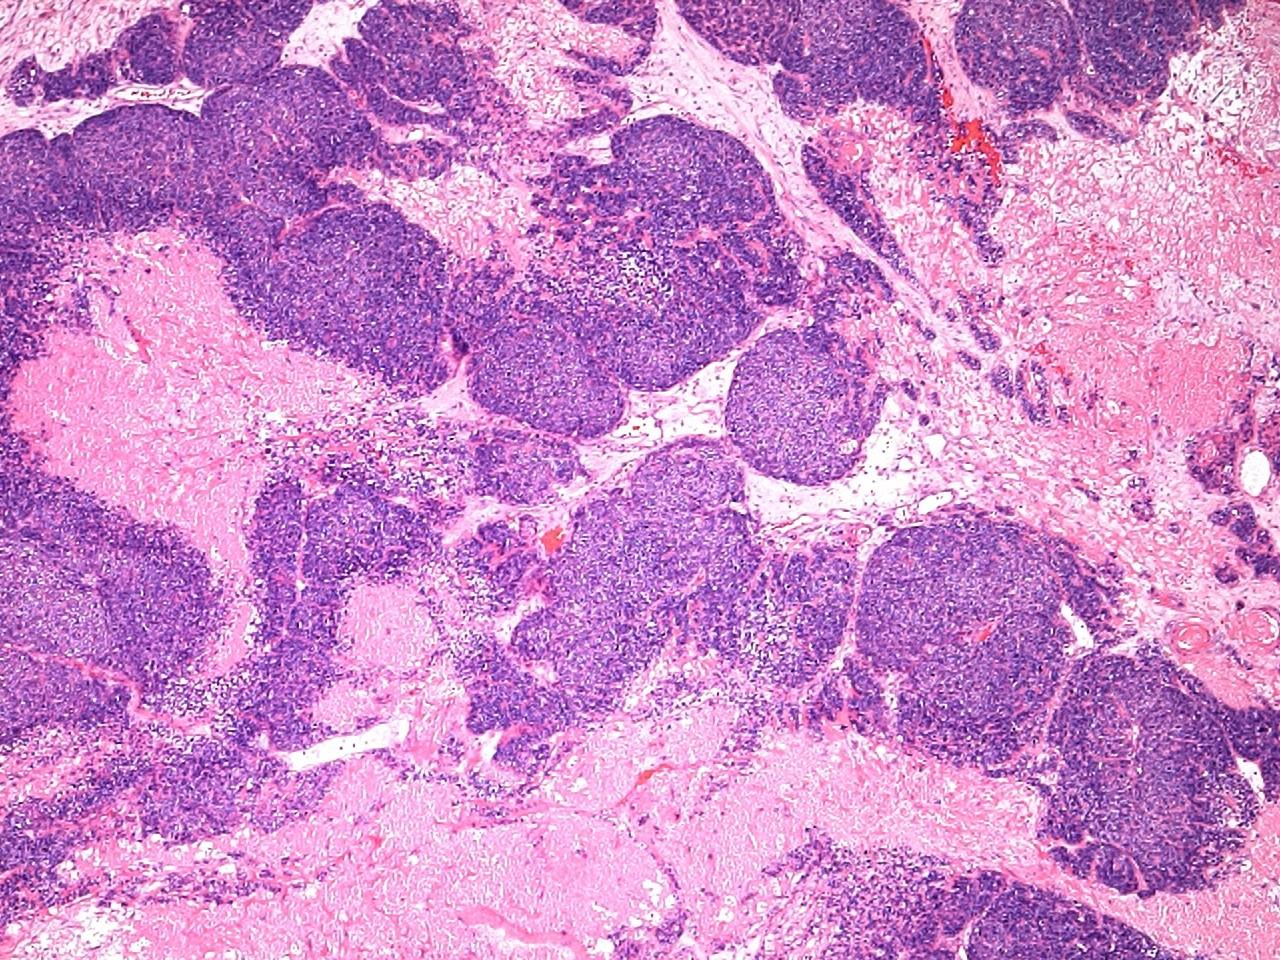

Olfactory neuroblastoma

 3rd – 4th decade

 Lobules of small blue round cells

 60-70% have a fibrillary stroma

 Rosettes: Homer - Wright or Flexner –Wintersteiner

 Neuroendocrine markers +

 Cytokeratins –

 S-100 scattered + cells at periphery of lobules

Differential diagnosis

Small cell carcinoma

SNUC

Rhabdomyosarcoma

ES / PNET

Melanoma

Lymphoma